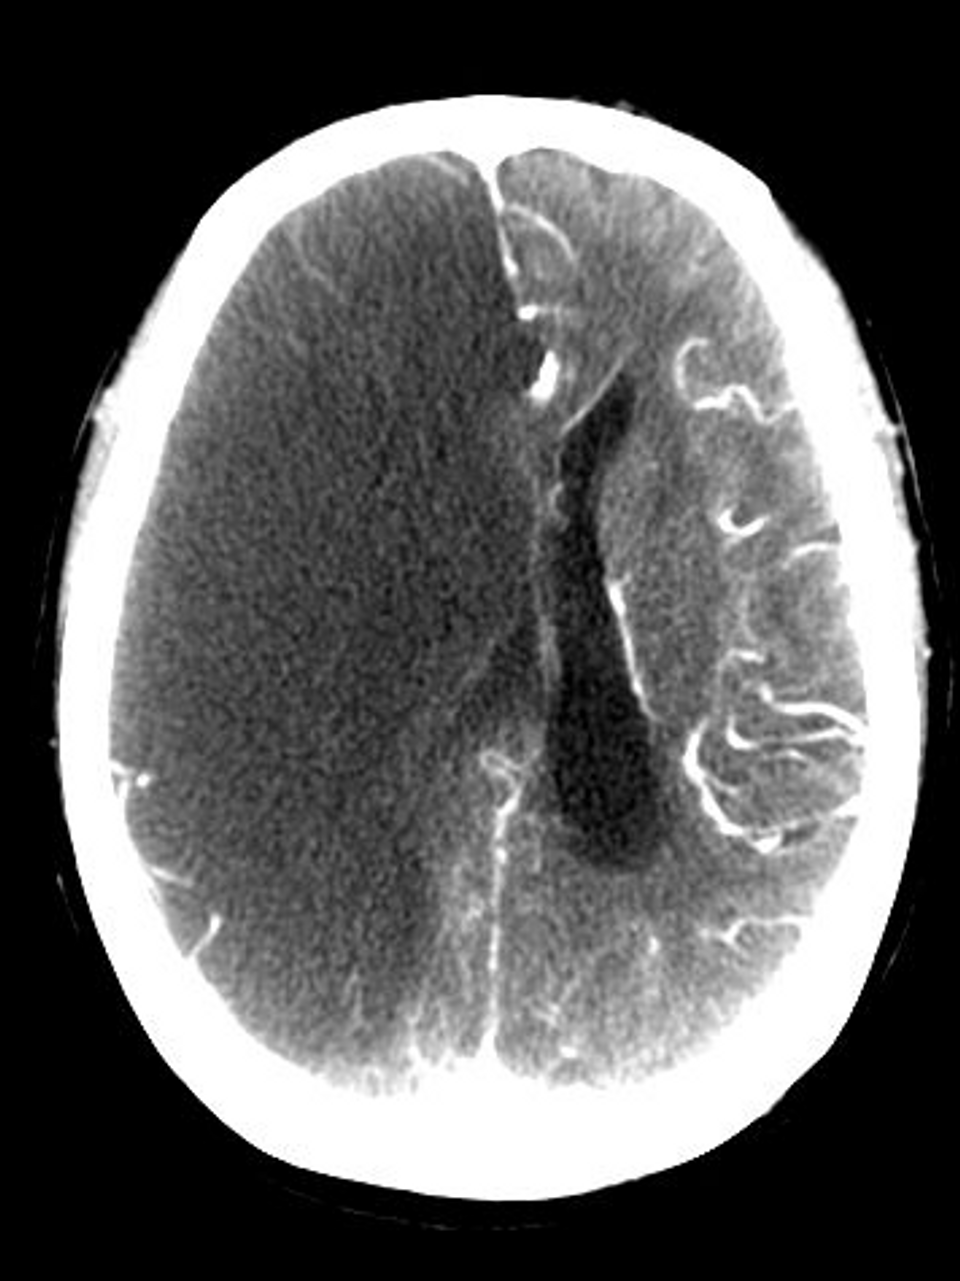

Does Covid 19 Cause Blood Clots In Brain

Why Is Covid 19 Coronavirus Causing Strokes In Young And Middle Aged People

Covid 19 May Increase Blood Clotting And Blockage Of Brain Blood Vessels

Ischemic Strokes Clots American Stroke Association